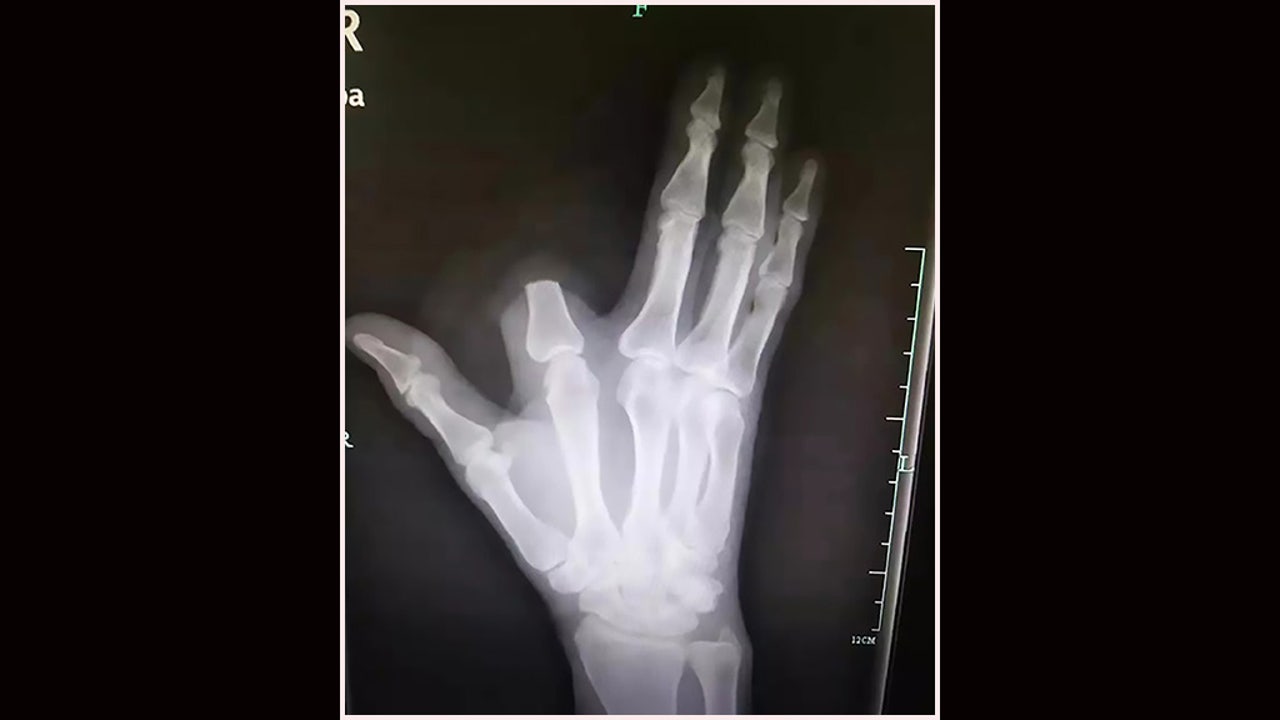

Doctors say a man in China hacked off his own finger after he was bitten by a snake that he believed was highly venomous. The man, identified as a 60-year-old named Zhang, reportedly claimed he was bitten on his index finger by a Deinagkistrodon acutus while working in the mountains.

Chengda, head of dermatology at Hangzhou Hospital of Traditional Chinese Medicine, said the man’s actions were “really unnecessary” and that they likely could have reattached his finger had the man brought it with him.